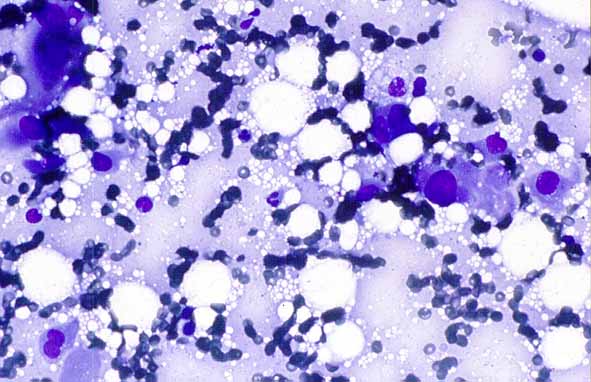

figura2.jpg (26685 bytes)

Figura 2. Metástasis de adenocarcinoma pulmonar.